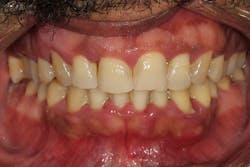

Treatment of the gummy smile due to gingival enlargement is dependent on the etiologic agent and the category the disease falls under. If the enlargement is induced by medication, suspension of the drug and institution of proper home care will resolve the problem. When caused by a systemic problem, treatment of the disease usually will result in treatment of the gingival enlargement. Hormonal fluctuations caused by pregnancy and puberty are often unavoidable; many times, gingival enlargement can be precluded/alleviated with excellent home care and routine dental maintenance visits. When these noninvasive modalities do not result in a resolution of the gingival enlargement, surgical treatment is often needed to remove excess tissue.